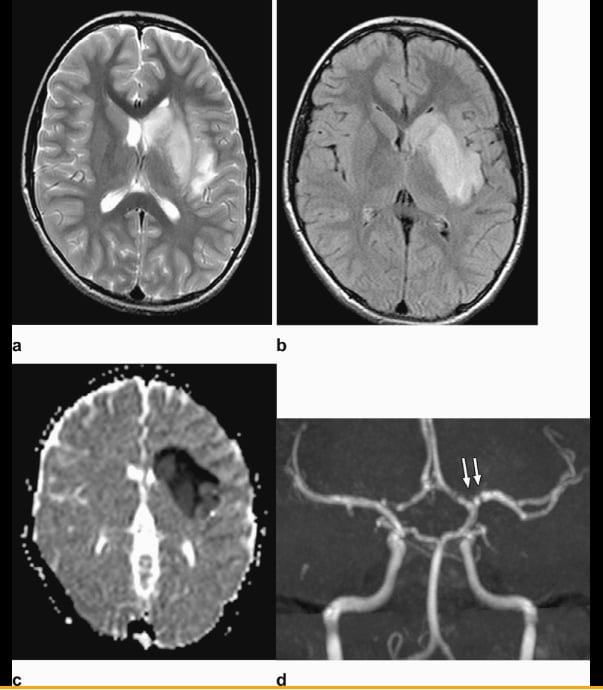

This photo gallery shows the variety of radiological presentations of COVID-19 (SARS-CoV-2) in medical imaging, including computed tomography (CT), radiograph X-rays, ultrasound, echocardiograms and magnetic resonance imaging (MRI). The radiology images show examples of typical COVID pneumonia in the lungs and the numerous complications the virus causes in the body in multiple organs, including the brain, kidneys, heart, abdomen and vascular system.